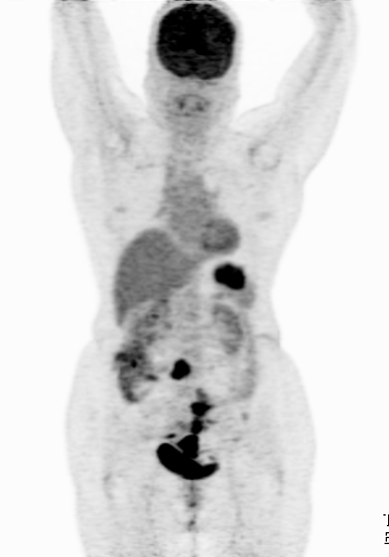

PET CT- POSITRON EMISSION TOMOGRAPHY

It is a non invasive technique for quantification of radioactivity after injection of radioactive substance in the body. it has various clinical applications especially oncologic imaging for diagnosis, staging and follow up for treatment response in cancer patients.

Non- oncologic applications are emerging gradually in cases of dementia and other neurological conditions.